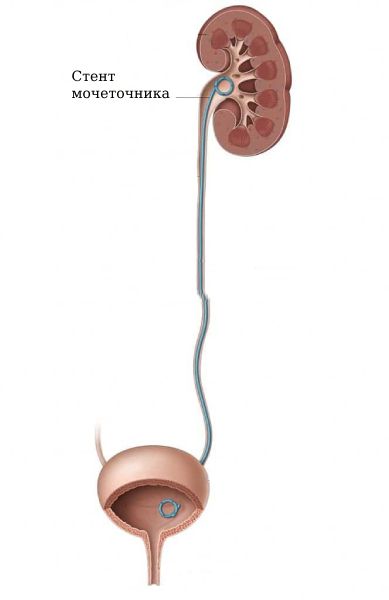

К стентированию мочеточника прибегают, когда отток мочи из почки затруднён. Во внутренний просвет мочеточника на всю его длину устанавливается тонкая полая трубка (стент). Верхний конец трубки располагается в лоханке почки, нижний выходит в полость мочевого пузыря. Введение стента позволяет восстановить нормальный отток мочи.

Стент, предназначенный для установки в мочеточник — это тонкая полая трубка. Чаще всего она изготавливается из силикона, полиуретана или термопластичных полимеров. Металлические стенты применяются реже. Трубка может быть армированной, иметь гидрофильное покрытие.

Мочеточниковые стенты бывают разных размеров и диаметра. Средняя длина изделия для взрослых — 24–28 см. После обследования органов малого таза (УЗИ, рентгенодиагностика) врач подбирает подходящий для пациента вариант.

Концы трубки обычно загнуты в форме буквы «J» либо спиралью, в виде так называемого «свиного хвоста» (pig tail). Это необходимо для того, чтобы стент не менял своего положения после установки. Существует несколько видов:

- Двухпетлевой: оба конца трубки загнуты. Верхний завиток располагается в просвете почечной лоханки, нижний выводится в мочевой пузырь.

Ретроградный способ при доступе через уретру — малоинвазивный. Применяется чаще всего, поскольку наименее травматичный. Манипуляция длится около получаса. Вмешательство может выполняться амбулаторно. В некоторых случаях врачи предпочитают госпитализировать пациента. Используется либо местная анестезия, либо наркоз. Не требуется никаких проколов или разрезов. В уретру вводится цистоскоп, оснащённый подсветкой и видеокамерой. Под контролем оптики стент вслед за проводником внедряется через уретру в мочевой пузырь, затем проталкивается в мочеточник. Верхний конец трубки размещается в лоханке почки, нижний остается в мочевом пузыре. Затем цистоскоп извлекается. Для дополнительного контроля положения трубки используют рентген.